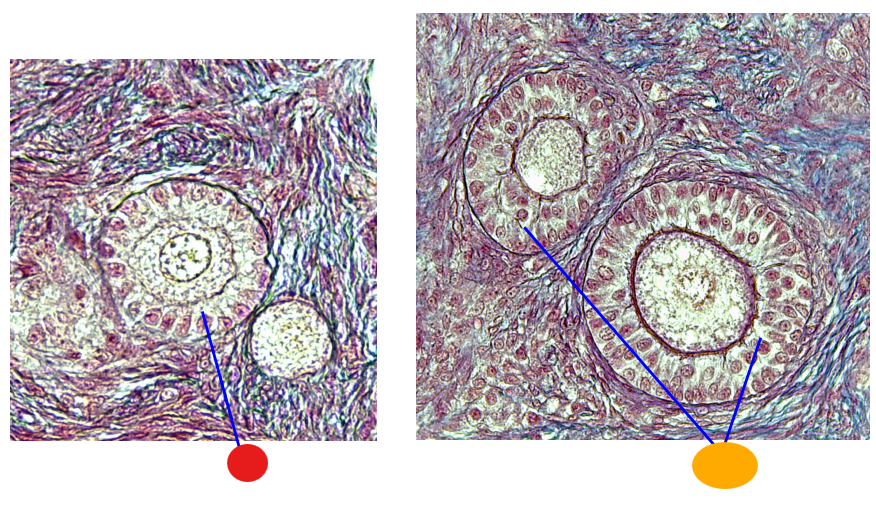

red

tunica albuginea

orange

primordial follicles

yellow

follicular cells

light green

primary oocyte

dark green

granulosa cells

light blue

primary follicles

what is this?

ovary

red

primordial follicles

red

primary follicles

red

tunica albuginea

orange

primary oocyte

yellow

primordial follicles

red

tunica albuginea

orange

primordial follicles

red

primary follicle

orange

secondary follicles